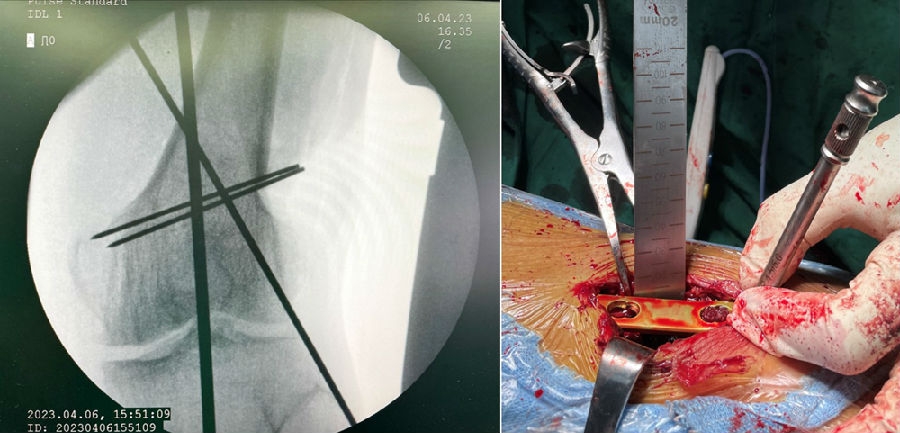

3、手术的关键

第一侧截骨要把关节线放平;第二侧截骨要达到整体目标力线。

经典病例